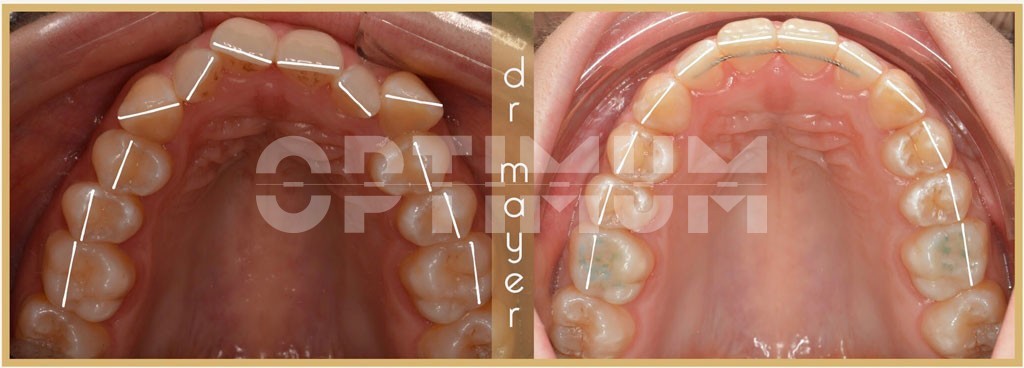

Páciensünk esztétikai fogszabályozás céljából kereste fel az OPTIMUM Fogászatot. Szájvizsgálat után a beszűkült alsó és felső fogívek miatt kialakult súlyos torlódást találtunk. A beszűkült fogívek miatt mosolygáskor kevés fog látszódott. A felső szemfogak teljesen kiszorultak a sorból. A fogívek előnytelen V alakúak voltak, mely miatt a felső metszőfogak előre állónak tűntek. Az oldalsó koponyaröntgen vizsgálata alátámasztotta, hogy a felső metszőfogak pozíciója arcesztétikai szempontokból is megfelelő.

Az egyértelmű volt, hogy alsó/felső rögzített fogszabályozó készülékre van szükségünk az megfelelő eredmény eléréséhez. Foghúzás évekkel ezelőtt szóba jöhetett volna, de ma már nem csak szabályos fogakat, hanem gyönyörű mosolyt is szeretnék pácienseimnek adni. Így szóba sem kerülhetett ép fogak eltávolítása. Lágyerővel működő, önligírozó, rögzített H4 készülék mellett döntöttünk. A modern kezelési elveknek és anyagoknak hála sikerült a fogíveket megtágítani és szép U alakú íveket kialakítani. Harapásemelők segítségével biztosítottuk, hogy könnyen és gyorsan tudjuk a fogíveket tágítani.